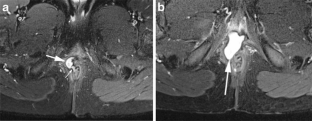

Perianal disease in pediatric Crohn disease: a review of MRI findings

Perianal complications of Crohn disease are a common occurrence in children and can result in significant morbidity when not accurately characterized prior to surgical intervention. MRI is an excellent imaging modality for the evaluation of perianal inflammatory bowel disease – allowing characterization and detailed description of perianal fistulas. MRI has many advantages over other imaging modalities for the pediatric patient. Radiologists will benefit from a sophisticated understanding of perianal anatomy, the classification of perianal fistulas, the advantages MRI offers in characterization of perianal fistulas as well as the common and incidental findings that are important in the MRI evaluation of perianal inflammatory bowel disease in children. Perianal fistulas are found at a high rate in pediatric referrals and are more commonly found in male patients.